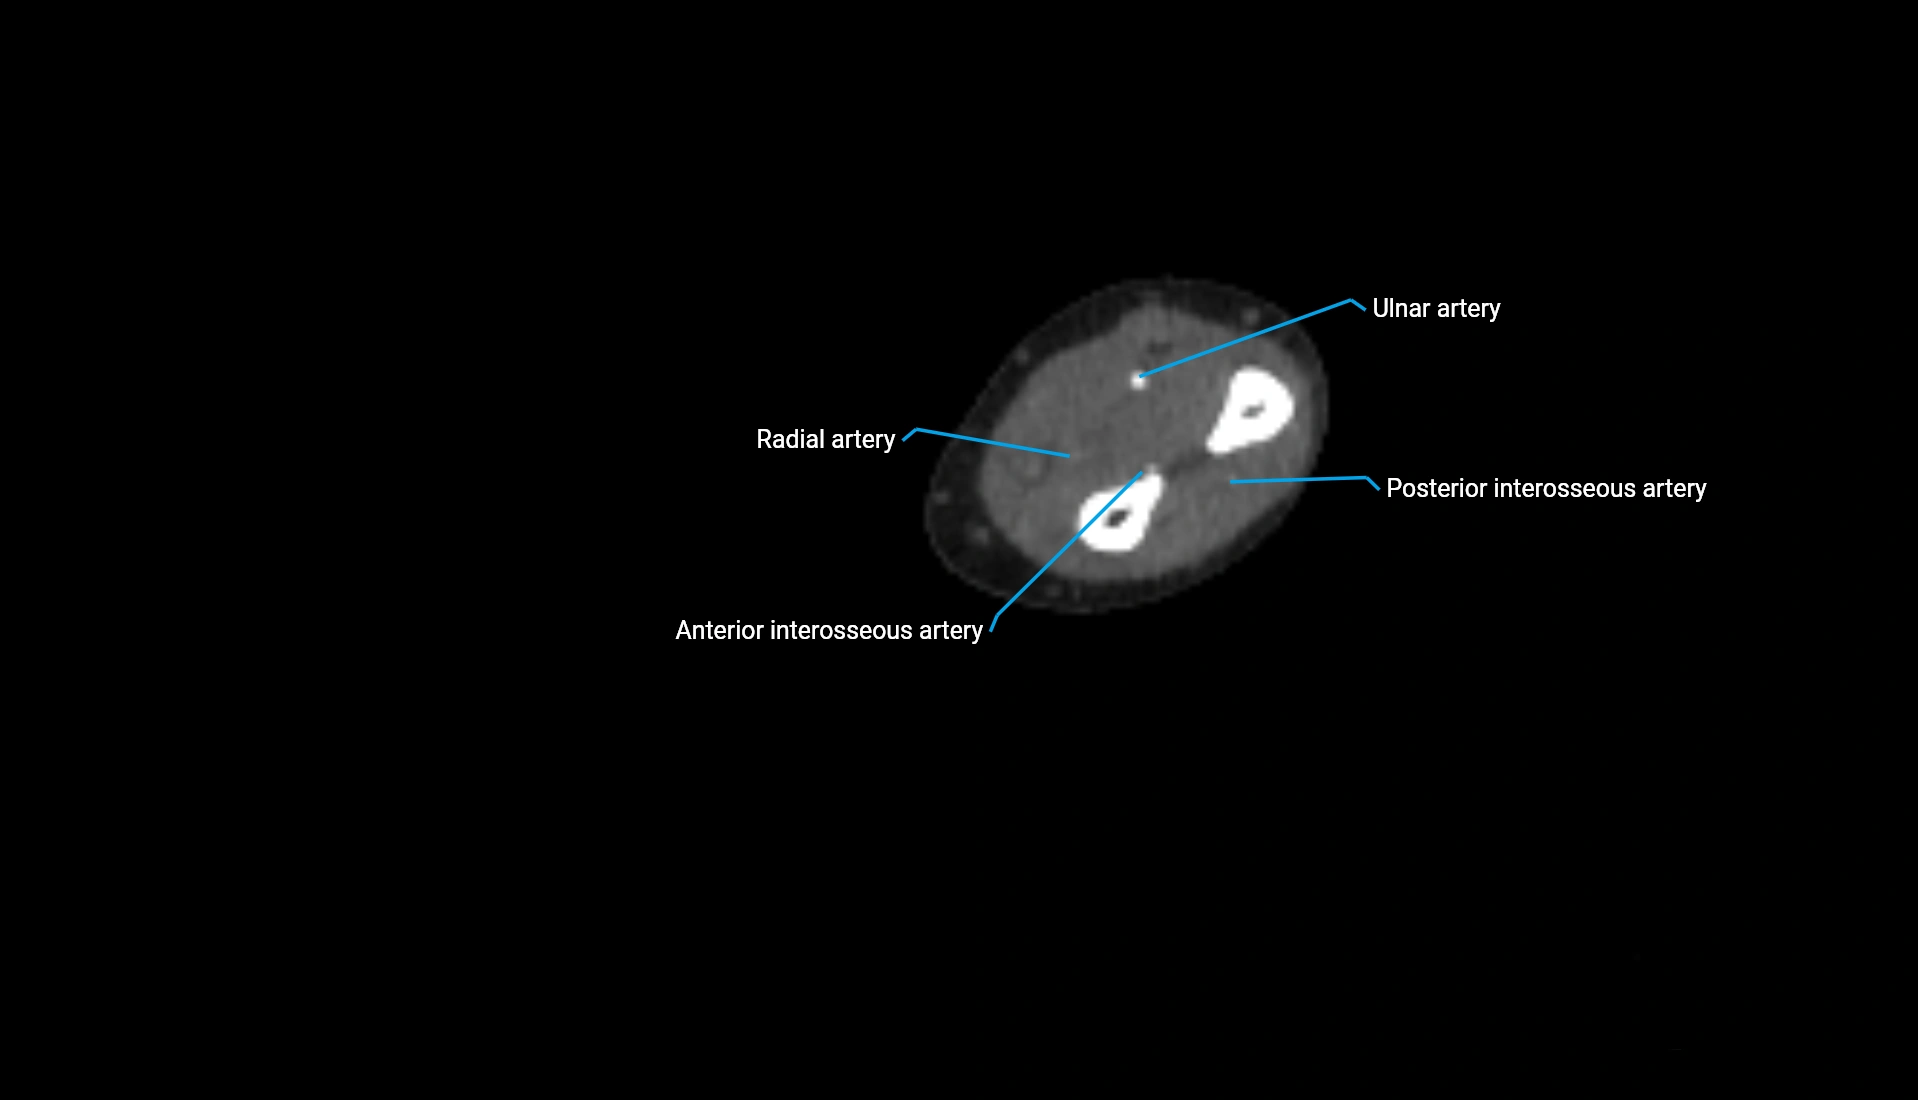

CT Appearance

Non-Contrast CT:

• Cortex: High-density, sharply defined

• Subchondral bone: Dense cancellous matrix

• Articular surface: Smooth concave contour articulating with the capitellum

• Excellent for evaluating bone integrity, alignment, and subtle fractures

Post-Contrast CT:

• Bone: No enhancement

• Joint capsule and synovium: Mild enhancement outlining the joint

• Improves contrast between soft tissues and bony margins

• Useful in detecting subtle joint abnormalities or postoperative changes